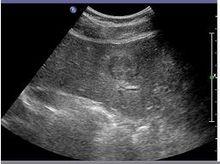

二維FNH通常表現為輕微的低回聲或等回聲,很少為高回聲,經常可見到分葉狀輪廓及低回聲聲暈,而腫塊內部回聲分布均勻,可有點線狀增強,邊緣清晰,無包膜,星狀瘢痕為輕微的高回聲。